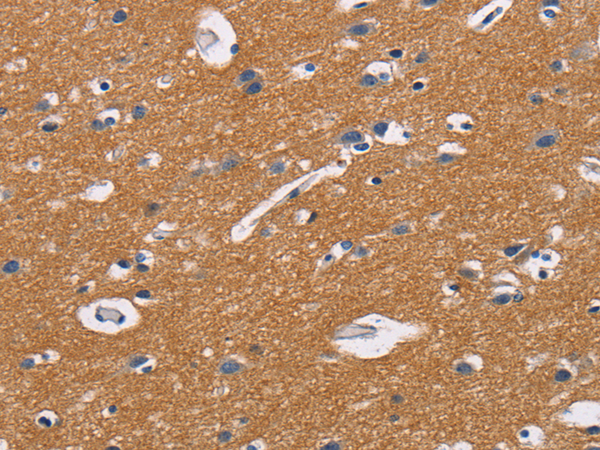

The image is immunohistochemistry of paraffin-embedded Human brain tissue using P11643(CD47 Antibody) at dilution 1/50. (Original magnification: ×200) |